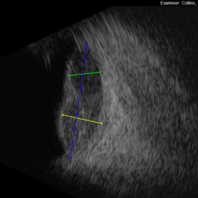

Large, Dome-Shaped Peripheral Choroidal Melanoma - B Scan

Large, Dome-Shaped Peripheral Choroidal Melanoma - B Scan

Feb 13 2020 by Michael Seider, MD

Large, dome-shaped peripheral choroidal melanoma of the left eye with inferior exudative retinal detachment. Note the lack of obvious orange pigment over the tumor and apparent drusen anteriorly. A lack of ophthalmoscopically obvious lipofuscin is not uncommon among larger choroidal melanomas. B-Scan ultrasonography (transverse, 10 o’clock) confirms a low-moderate internally reflective dome-shaped choroidal lesion with a small adjacent retinal detachment. Ultrasound biomicroscopy (radial, 10 o’clock) confirms no ciliary body involvement of the tumor.